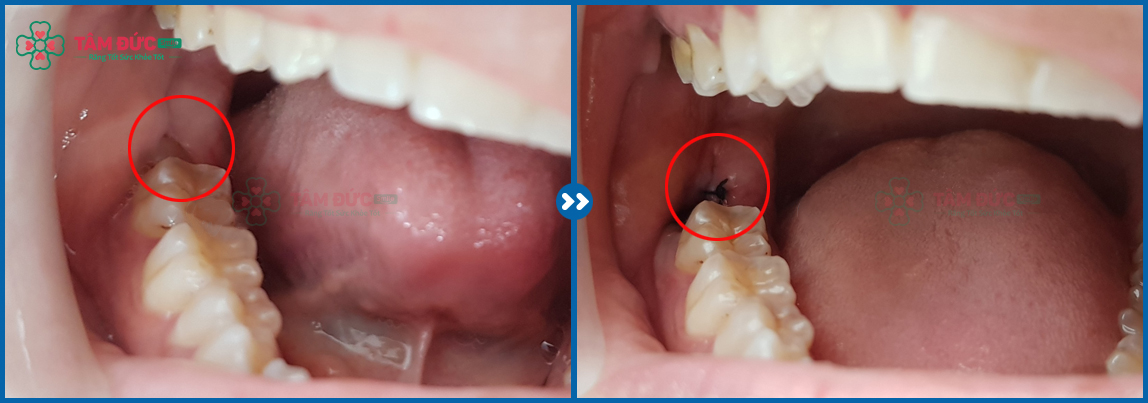

✔ Impacted wisdom tooth

✔ Embedded wisdom tooth

✔ Partially erupted or fused wisdom tooth

Most cases of wisdom teeth eruption involve abnormalities such as impacted, embedded, or fused teeth, making surgical extraction necessary in these situations.